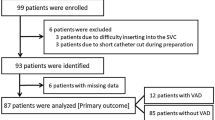

From June 2016 to October 2017, 210 patients were enrolled at a single German center and randomly assigned to undergo PICC implantation under either fluoroscopic control or by means of magnetic tracking and ECG-guided TCS (Fig. 2). Patient characteristics of the two groups were well matched at baseline (mean age 62.3 ± 14.4 years, 134 [63.8%] male, mean BMI 25.7 ± 6.1 kg/m2). Insertion of PICC using TCS took significantly longer compared to fluoroscopy (8.4 ± 3.7 min vs. 5.0 ± 2.7 min, p < 0.001) (Table 1).

Incidence of correct PICC tip position was 82.4% (84 of 102) in the TCS group and 99.0% (103 of 104) in the fluoroscopy group. The lower bound of a one-sided 95% confidence interval (CI) of −23.1% difference in proportions of proper tip position was below the prespecified boundary of −5%. Thus, noninferiority of TCS compared to fluoroscopy was not established (p value for noninferiority: > 0.99). The two-sided 95% CI was entirely below the noninferior margin, and therefore demonstrated inferiority of TCS over fluoroscopy (−16.7% [95% CI −24.3 to −9.1%], p < 0.001) (Fig. 3). Logistic regression revealed an increased odds for malposition in obese patients (odds ratio 2.9 [95% CI 1.1 to 7.9], p = 0.04). However, age, sex, and BMI did not interact with the effect of TCS (Fig. 3). Five of 18 cases of incorrect tip position in the TCS group (27.8%) were associated with a weak signal of the TCS. In 12 of 17 cases of weak TCS signal, a correct tip position was achieved based on ECG guidance alone. Weak signal was not significantly associated with obesity (odds ratio 1.3 [95% CI 0.4 to 4.6], p = 0.67).